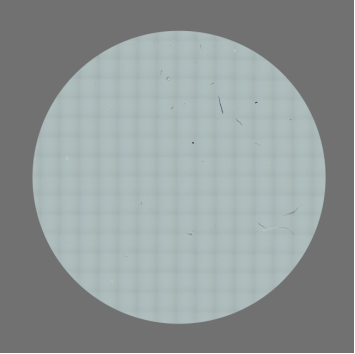

2.過濾與濾膜處理:用適宜轉移容器量取不少于25ml供試液,沿濾器內壁緩慢注入預處理后的濾器,緩慢抽濾至濾膜近干;若供試劑量超出漏斗容積,需分批注入完成抽濾。之后用25ml微粒檢查用水洗滌過濾漏斗,繼續抽濾至濾膜近干。保持抽濾狀態移去漏斗并關閉真空泵,用平頭鑷子將濾膜移至平皿,必要時涂抹極薄層甘油使濾膜平整,微啟平皿蓋子待濾膜適當干燥后閉合。

3.顯微計數:將平皿置于顯微鏡載物臺,調好入射光,以100倍或適宜倍數放大,待濾膜格柵清晰后,移動坐標軸,逐一計數有效過濾面積上最長粒徑大于規定粒徑的微粒數量。平行試驗兩份,最終結果以兩次測定的平均值為準。